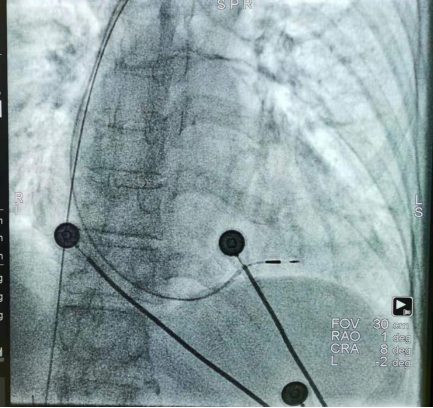

图二:术后X影像,提示心室电极固定在室间隔中部(为左束支区域起搏的理想解剖位点)

2021年7月24日,经过详细的术前讨论和严密的技术准备,由心血管内科二病区邓小军主任医师,刘盼副主任医师组成的介入手术团队成功为患者实施左束支区域起搏。手术过程顺利,术后患者恢复良好,起搏器工作正常,无不适。